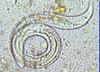

What is being shown here that is acquired from eating poorly cooked shellfish?

Paragonimus (lung fluke)